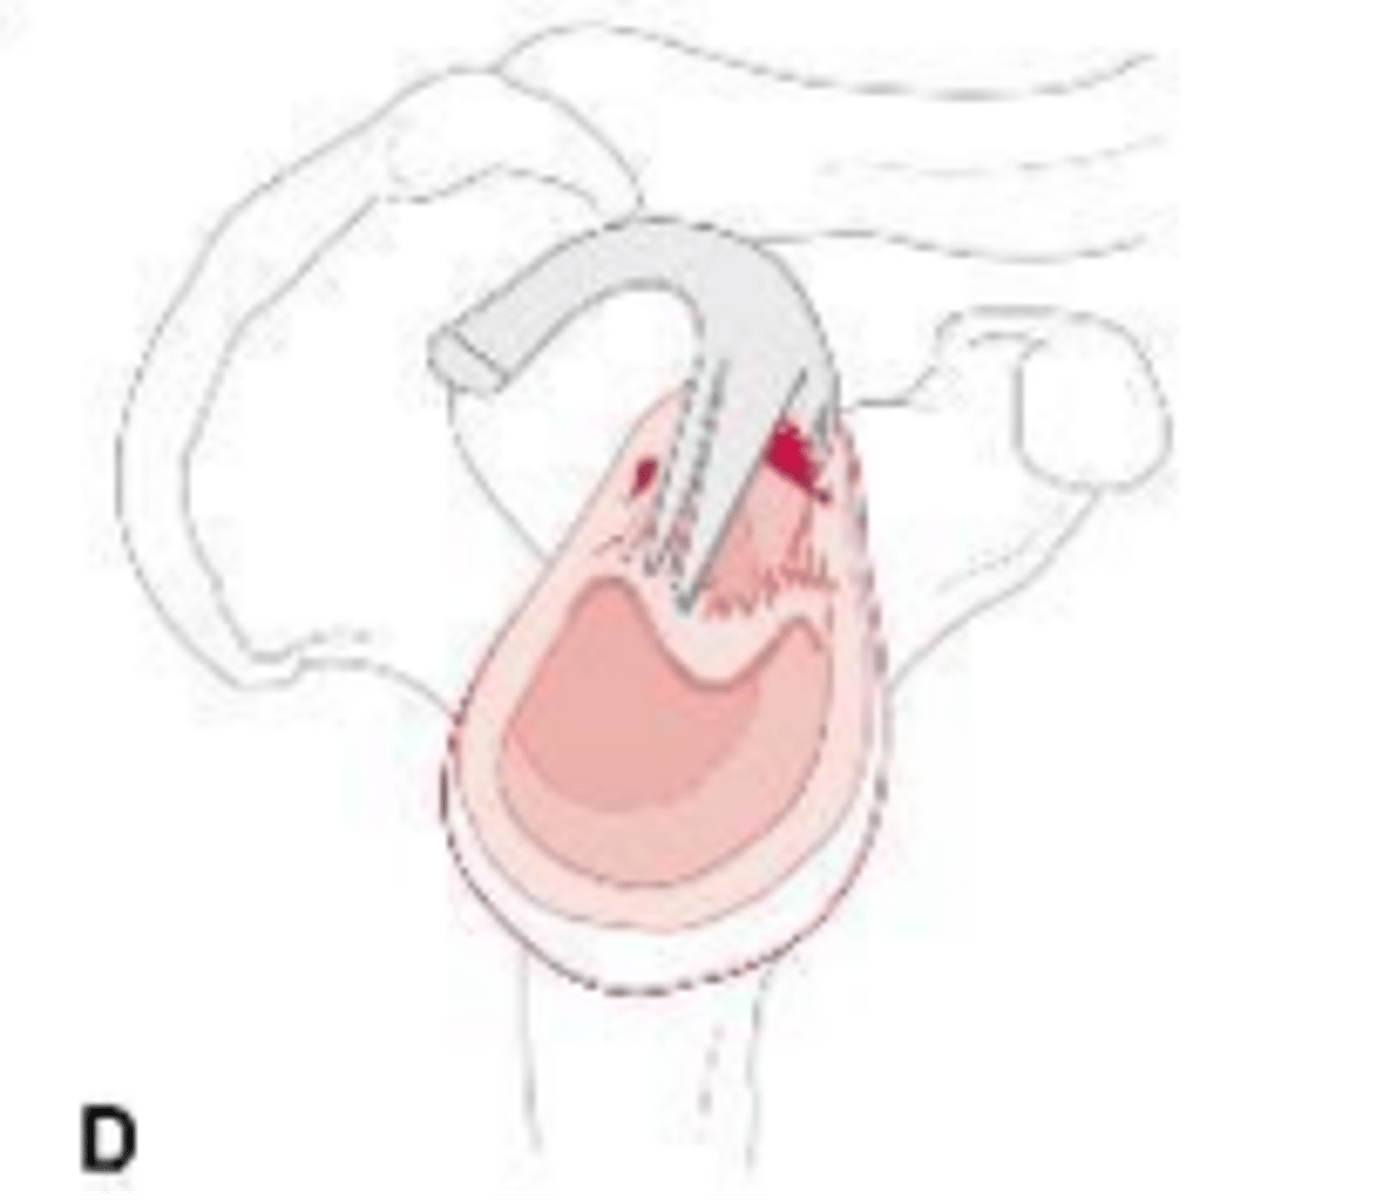

Tissue flap-bucket handle tear of labrum, tear extended into biceps tendon, stable or unstable labrum/biceps complex on the glenoid

What does the image show?